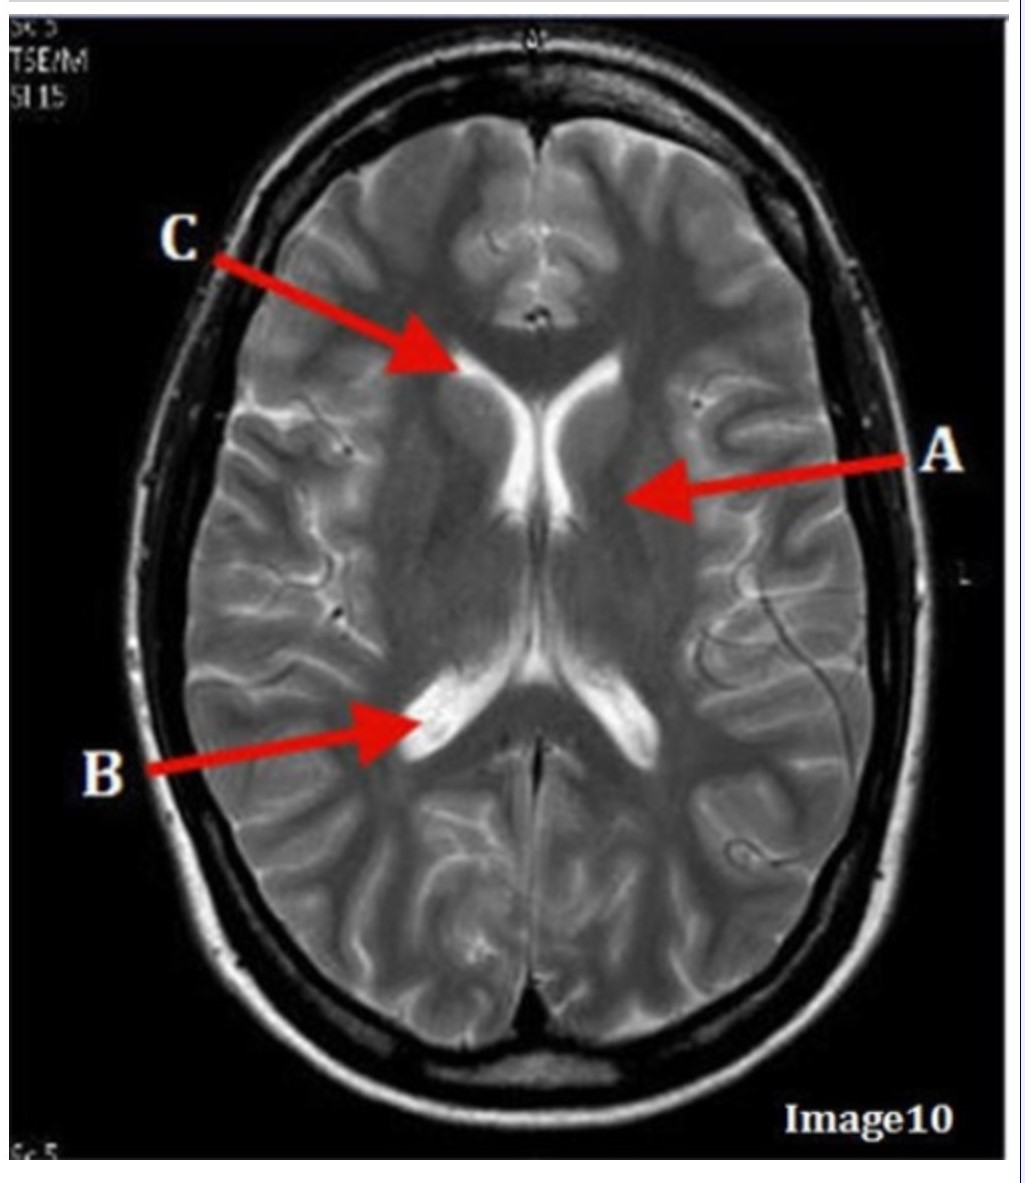

Letter B in Image 10 is pointing to:

A. Third ventricle

B. Basal ganglia

C. Anterior horn lateral ventricle

D. Posterior horn lateral ventricle

Letter C in Image 10 is pointing to:

A. Third ventricle

B. Basal ganglia

C. Anterior horn lateral ventricle

D. Posterior horn lateral ventricle

Letter A in Image 10 is pointing to:

A. Third ventricle

B. Basal ganglia

C. Anterior horn lateral ventricle

D. Posterior horn lateral ventricle

Image 9 is an example of a _____ weighted sequence acquired in the _______ scan plane.

A. T1; Axial

B. T2 FLAIR; Sagittal

C. T2; Axial

D. T2; Coronal